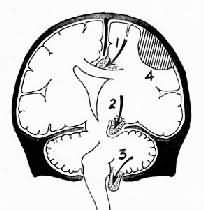

图16-6 脑疝模式图

1.扣带回疝;2.海马钩回疝;3.小脑扁桃体疝;4.硬膜外血肿